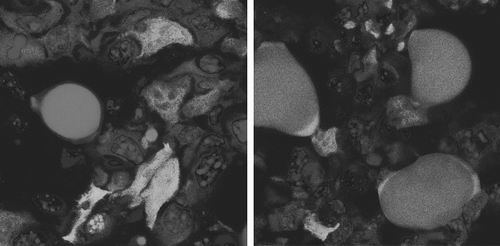

图片来源:《细胞》当癌细胞对微环境中的信号做出反应时,它们就会进入高度可塑状态,在这种状态下,它们很容易转化为另一种类型的细胞。瑞士研究人员利用上皮—间质转化(EMT),诱导小鼠乳腺癌细胞转化为无害的脂肪细胞。这项概念验证研究发表在近日的《癌细胞》上。论文第一作者、巴塞尔大学生物化学教授Gerhard Christofori说:“乳腺癌细胞不仅分化成脂肪细胞,而且完全停止了增殖。”此外,原发肿瘤未发生转移。“据我们所知,长期培养实验显示,从癌细胞转化成的脂肪细胞能保持脂肪细胞状态,并且不会恢复到乳腺癌细胞。”他说。EMT对胚胎发育和组织再生(如伤口愈合)至关重要。胚胎发育期间,干细胞分化为全身各种细胞类型。而且,EMT和相反的过程,即间充质—上皮转化(MET),与癌症的转移能力有关。Christofori说,经历EMT或MET的细胞处于高度可变的状态,这为治疗靶向提供了一个机会。研究人员在小鼠模型中对转移性乳腺癌进行了测试。当这些小鼠接受两种美国食品药品监督管理局批准的药物—— 一种癌症抑制剂和一种抗糖尿病药物治疗时,这些侵袭性癌细胞会转化为脂肪细胞。这些药物还能抑制小鼠体内原发性肿瘤的生长,并防止肿瘤向全身扩散。研究人员还瞄准了少数已经离开原发肿瘤并侵入周围组织的癌细胞。这些细胞很可能经历过EMT,因此很容易转化为脂肪细胞,而肿瘤内剩余的癌细胞不再无限制地增殖。研究人员假设,迫使临界数量的癌细胞分化成脂肪细胞,可能会削弱肿瘤抵抗传统化疗的能力。下一步,研究人员计划结合现有的化疗和其他类型的癌症测试EMT靶向分化方法。(来源:中国科学报 唐一尘)相关论文信息:DOI: 10.1016/j.ccell.2018.12.002 研究诱导小鼠乳腺癌细胞转化为无害的脂肪细胞